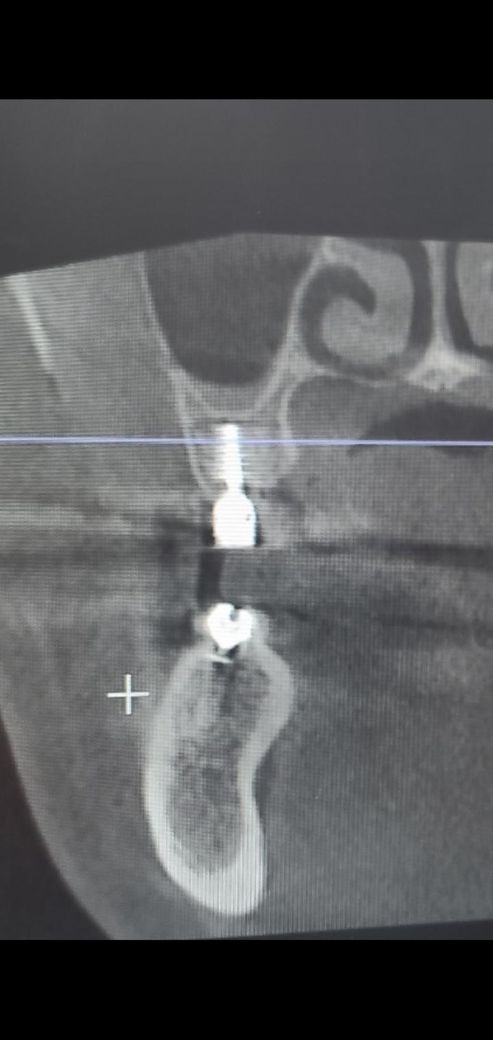

임플란트 상악동 문제는 없는건지요?

17번 오른쪽 위에 맨 끝부분에 임플란트가 현재 보철이 올라온 상태 인데 씹을때 통증이 있고 오른쪽 편두통 까지 오네요

16번과 17번은 상악동 거상술로 인하여 뼈이식을 같이 한다고 하여 1개 값 50만원을 지불 했었고요, ct 상으로 16번, 17번 임플란트 상악동 뼈이식 수술이 잘되었는지 봐주시길 요망합니다. 현재 17번 제거를 심각하게 고려중이 라서요...

엑스레이 상으로는 상악동 거상술 및 뼈이식이 잘된거 같습니다. 보철물이 올라간지 얼마 안됫다면 오랜기간동안 치아를 사용하지 않아서 적응하는데 불편감이 잇을수 있습니다.

임플란트 상악동 문제는 없는건지요? -> 첨부된 엑스레이 사진상 큰 문제는 없어 보입니다, 상악동 뼈이식은 ct 단면상 16번쪽을 봐야 알 수 있습니다